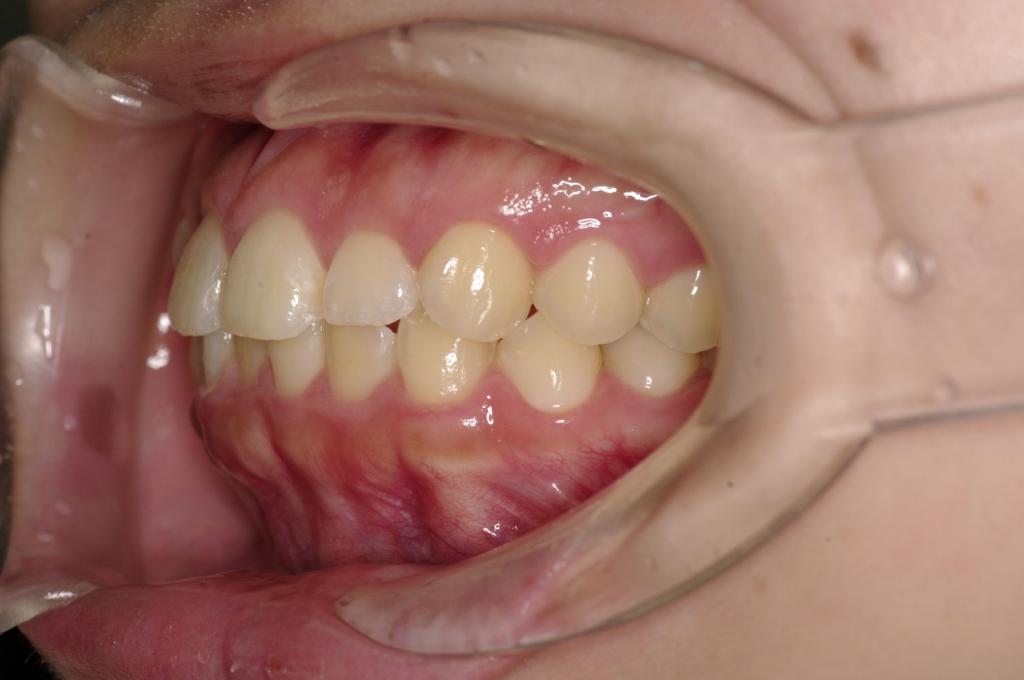

前歯、出っ歯・開咬の矯正治療

(治療期間、治療前後写真、治療方法、費用)WORKS